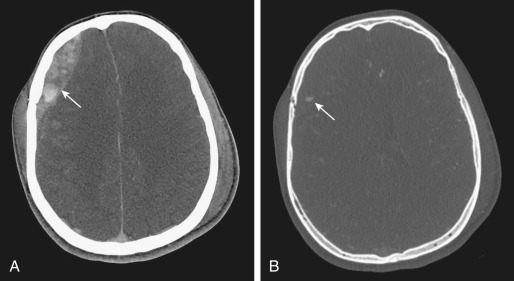

EDH